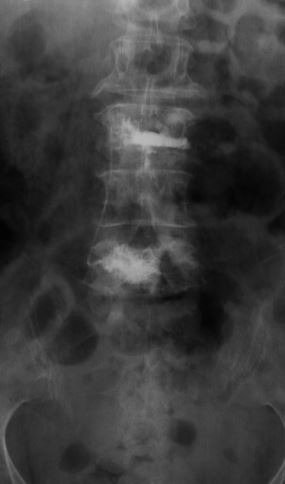

Another example is a young lady who had severe low back pain. Traditionally, fusion surgery through very large incisions would be required. With the new “percutaneous” technique of placement of pedicle screws, we were able to remove her disc through her abdomen and place screws through two small incisions in her back. She is now more than 80% improved.*